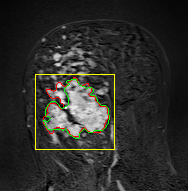

In MR images, tumor regions are normally brighter and have more uniform intensity than the neighbouring healthy tissue. Based on this fact, we determined the internal and external markers by sorting out the pixel values in ROIs in descending order and chose pixels with maximum intensity values as markers. After selecting the markers the normal watershed transformation is applied on the ROIs image which is shown in Fig 1 Finally, a binary mask is generated based on watershed output regions. However, we identified the optimal number of markers based on segmentation accuracy evaluated using Dice and Jaccard.

We tested the algorithm by varying the number of markers between and . Fig 2 describes the segmentation results obtained using different numbers of markers. This plot indicates that markers were found to be optimal using this segmentation approach, yielding satisfactory results.

where refers to the ROIs segmented by our algorithm and is tumor area as determined by manual segmentation. Table 1 summarizes the segmentation accuracy achieved using the proposed method for all 106 cases. The average dice coefficient was found to be 0.780.17 and average Jaccard index was 0.670.21. Fig 3 demonstrate four sample segmentation outputs which are overlaid on manual segmentations provided by two radiologists. It can be seen, that the proposed method could accurately segment the lesions with some marginal errors for medium to large tumors. However, for cases comprising disjoint lesions, the method failed to segment all small lesions and in some cases incorrectly labeled healthy tissue as lesions. This is because in some cases there is a high degree of overlap in the intensity distributions of healthy breast tissue and lesions, and the ROI drawn by the radiologist is very large in the case of disjoint lesions, in order to cover the entire area over which multiple lesions are distributed.